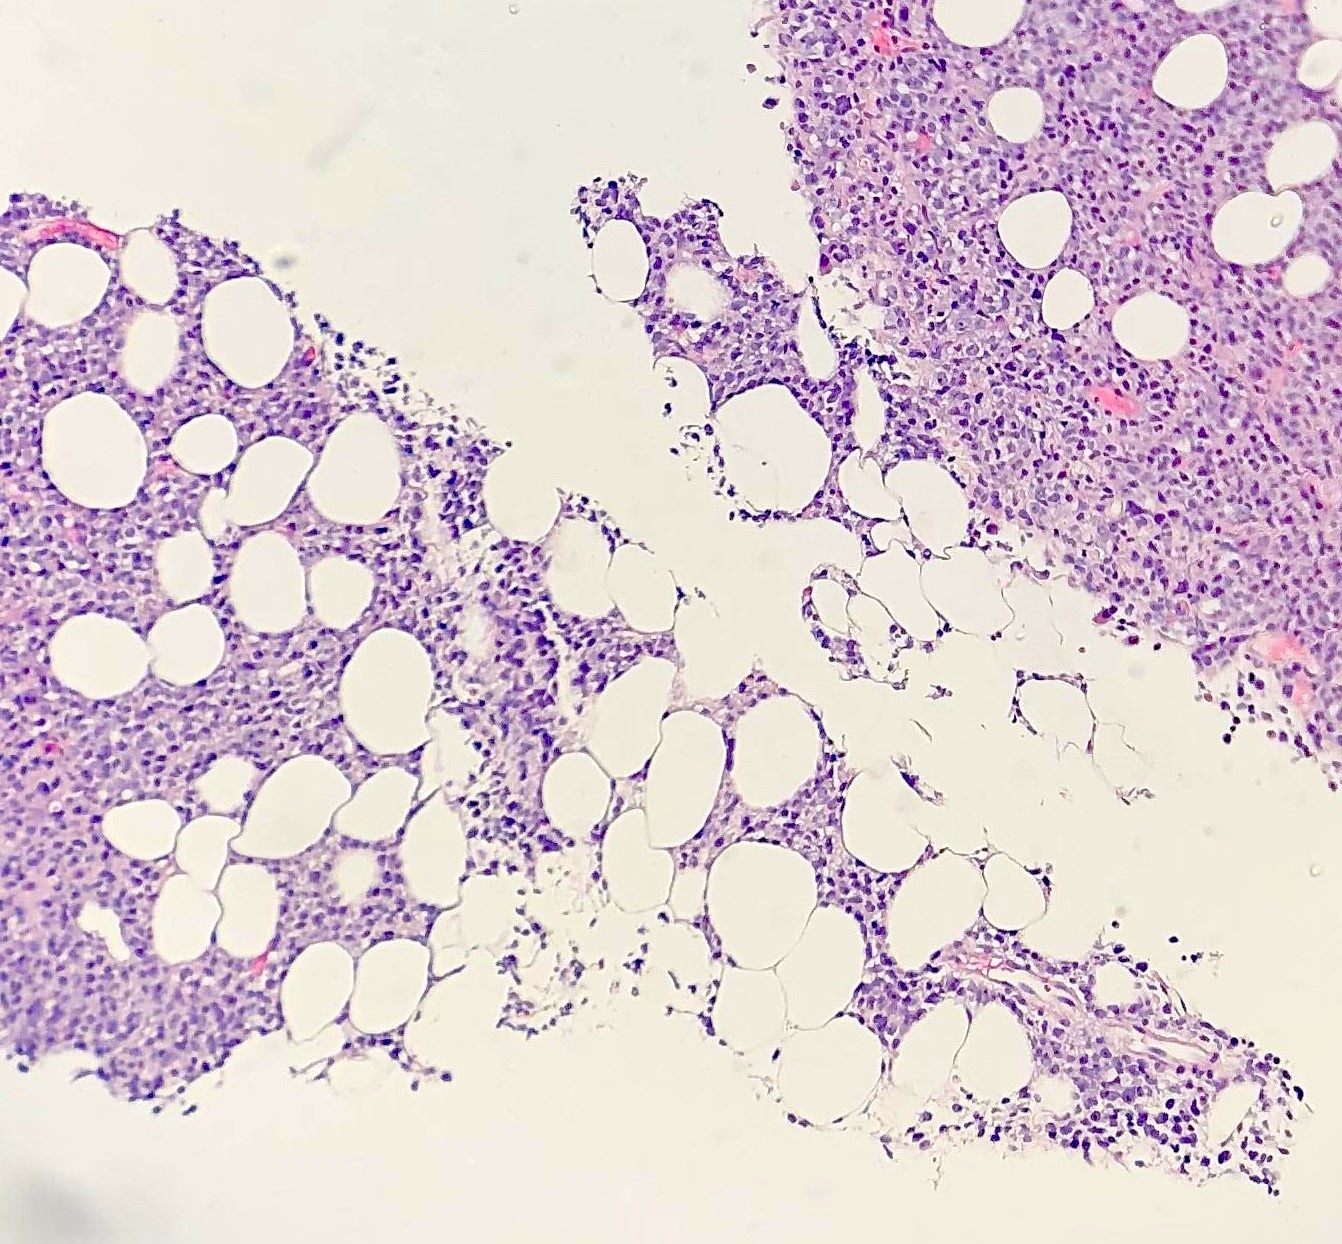

- Bone marrow involvement in 16% (J Clin Oncol 1998;16:2780)

Microscopic (histologic) description

- Partial or complete effacement of normal tissue architecture by a diffuse infiltrate of large (or occasionally medium size) atypical B lymphoid cells with vesicular chromatin and prominent nucleoli

Microscopic (histologic) images